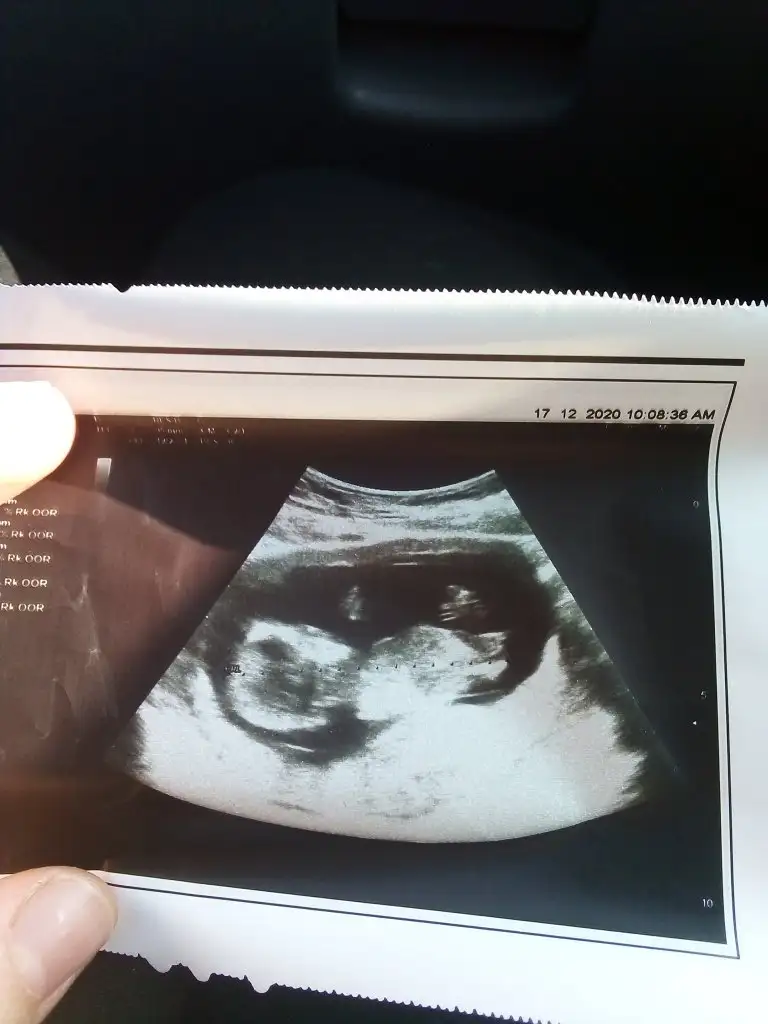

USG fotografinda Kaç haftalık?Teşekkürler Dr kız tahminim dedi ilerki haftalarda İnş kesin öğreniriz

Kızdır o zamanTeşekkürler Dr kız tahminim dedi ilerki haftalarda İnş kesin öğreniriz

Ogrendinizmi erkek demiştim sizemerhaba nub teorisine göre baktığımda kızım olacağını düşünmüştüm bugün doktorum çok yoğundu ve pek ilgilenmedi açıkçası ve cinsiyetini göstermiyor ama ben tahmin edeyim mi dedi. buyrun dedim erkek dedi. Sizler ne diyorsunuz ?Eki Görüntüle 2711512

Hep bir kızım olmasını istemişimdir ama öğrendiğimden beri erkek hissediyorum kese şekli, kesede ki pozisyonu, büyüme hızına bakıncada erkek bence deBuna göre erkek tabiki en iyi 11 12 13 haftalar olmalı